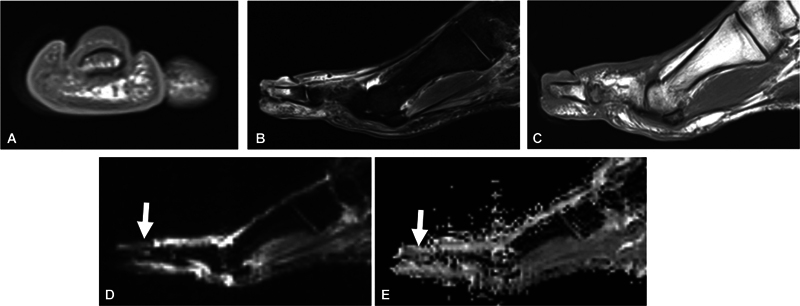

Objective  The aim of this study was to determine the sensitivity and specificity and inter-reader reliability of previously known "ghost sign" and "penumbra sign" on T1-weighted (T1W) imaging and "ghost sign" on apparent diffusion coefficient (ADC) map in osteomyelitis (OM) of the extremities. Materials and Methods  In this cross-sectional retrospective study, two fellowship-trained musculoskeletal readers blinded to final diagnosis of OM versus no OM were asked to report the penumbra sign and ghost sign on T1W images and ghost sign on ADC map, as well as diagnosis of OM. Cohen's kappa was used. Diagnostic performance measures including sensitivity, specificity, and accuracy were calculated. Results  A sample of 178 magnetic resonance imaging (MRI) scans of pathology-proven cases were included in this study, with 41 being positive for OM and 137 being negative for OM. There was a fair inter-reader agreement for imaging signs, and moderate agreement of 0.60 for OM. The sensitivities of the penumbra sign on T1W imaging, ghost sign on T1W imaging, and ghost sign on ADC map for OM are 3.7, 9.8, and 19.5%, respectively, while their respective specificities are 98.9, 97.8, and 94.5%, respectively. All three imaging signs showed a similar (good) accuracy of 76 to 78%. Conclusion  The ghost sign on ADC can be used as an additional marker for OM and is a similarly highly specific but a more sensitive sign for OM than the conventionally used penumbra sign and ghost sign on T1W imaging. Key Points The ghost sign on ADC can be used as a helpful indicator of osteomyelitis.Across two fellowship-trained musculoskeletal readers, there was a fair inter-reader agreement for imaging signs and moderate agreement for OM.The ghost sign on ADC is a similarly highly specific but a more sensitive sign for osteomyelitis than the conventionally used penumbra sign and ghost sign on T1W imaging. All three imaging signs showed a similar (good) accuracy of 76 to 78%.

Abstract Image